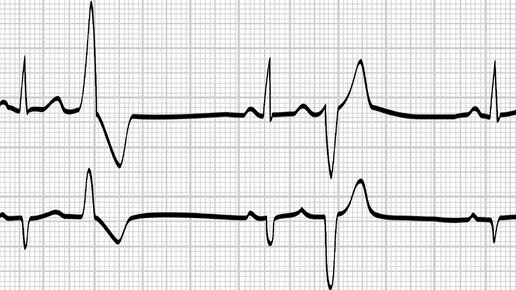

Одним из видов аритмий является экстрасистолия, внеочередное сокращение сердца, нарушающее кровообращение тканей. Среди всех вариантов аритмий отдельно выделяют экстрасистолии. Это внеочередное сердечное сокращение или патологическая активность отдельных его камер. Частые экстрасистолы могут приводить к выраженному нарушению кровообращения, в том числе в области мозга и других жизненно важных органов. При развитии экстрасистолии могут быть выраженная слабость, обмороки, зрительные расстройства, иные симптомы...

Экстрасистолы: какие они бывают, почему возникают, и стоит ли их бояться? Сегодня обсудим одно из самых распространенных нарушений сердечного ритма — экстрасистолию. Это состояние встречается у большинства людей и зачастую проходит незамеченным. Экстрасистолия — это внеочередное сокращение сердца, возникающее по разным причинам. Важно понимать, что экстрасистолы бывают двух основных типов: наджелудочковые и желудочковые. Подробное описание отличий можно прочитать в статье "Путеводитель по аритмиям" Подписывайтесь на блог — это мотивирует меня писать больше...